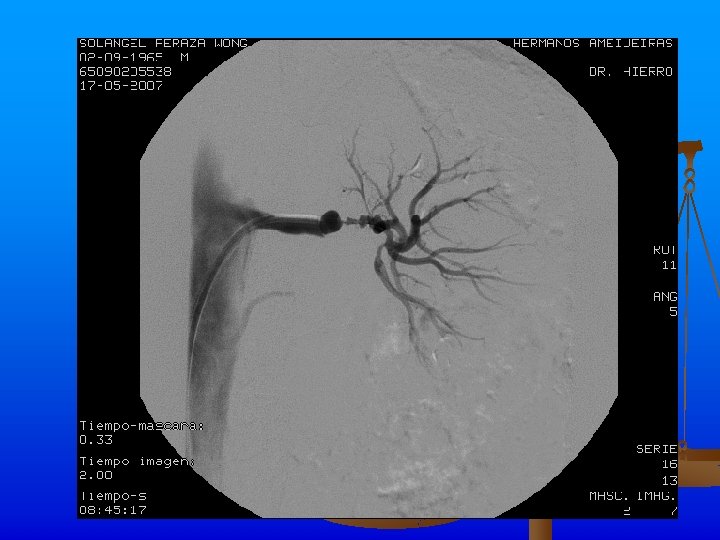

Exámenes Complementarios n n n Rx de tórax: Ligeros signos de hiperinsuflaciòn pulmonar. ICT normal. Índice de presiones de MI dentro de límites normales. Angio TAC: Se realiza angio. TAC abdominal inyectándose 120 ml de contraste, apreciándose áreas de estenosis y dilatación de ambas arterias renales, con un patrón arrosariado y zonas de hipoperfusión corticales en los polos de ambos riñones. Hay buena eliminación y concentración renal bilateral.

Se realiza angiplastia transluminar percutànea de arteria renal izquierda y se coloca stent de 18 X 4 mm con la administración de 1000 Uds. de heparina y la administración de contraste sin complicaciones